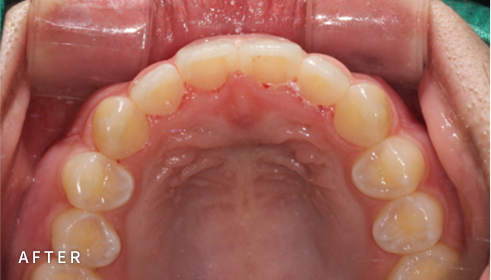

성인 & 성장기 어린이 모두

인비절라인으로 아름답게

인비절라인은 치아 배열 상태를 분석 및 예측하여 제작하는

환자 맞춤형 투명 교정장치입니다.

라인드치과는 성인과 성장기, 각각의 특성을 반영한

교정 플랜을 바탕으로

성인 ‘인비절라인’ 교정과

성장기 ‘인비절라인 퍼스트’ 교정 치료가 가능한 치과입니다.